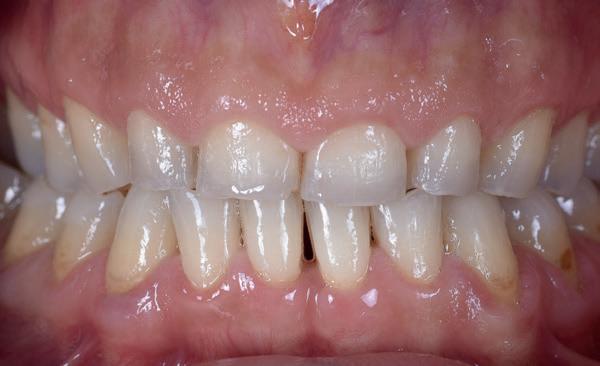

• Onbekende etiologie

In alle bovengenoemde gevallen is het goed om te overleggen met de tandarts wanneer hij wenst in te grijpen bijvoorbeeld zoals zichtbaar op afbeelding 13 en 14. Wanneer er nog sprake is van cuspidaatgeleiding kan je besluiten om dit te monitoren en splint therapie te adviseren. Maar wanneer cuspidaatgeleiding verdwijnt en overgaat in groepsgeleiding zal de tandarts de cuspidaat kunnen opbouwen en vervolgens een splint aanmeten. Dit zijn zaken die een mondhygiënist ook kan herkennen. Evenals afbeelding 14 waar sprake is van een constricted envelope of function. Dit houdt in dat iemand zichzelf op slot zet, waardoor vaak sneller slijtage ontstaat palatinaal van het bovenfront en buccaal van het onderfront. Dit verdient aandacht en dient, nog voordat de eerste tekenen van slijtage optreden, een red flag te zijn en besproken te worden met de tandarts en de patiënt.

• Keramiek is slijtvaster en esthetischer, maar duurder en wordt veelal gebruikt bij slijtage die al ernstiger vormen heeft aangenomen of als er reeds grote restauraties aanwezig zijn of endodontische behandelingen zijn uitgevoerd. Complexere gevallen vereisen soms een volledige reconstructie, waarbij de verticale dimensie van occlusie wordt verhoogd (afbeelding 15 waar ook reeds dentoalveolaire compensatie heeft opgetreden). De keuze tussen directe en indirecte technieken hangt af van het aantal betrokken elementen, de esthetische wensen van de patiënt de mate van slijtage of de financiële draagkracht. Echter, bij ernstige slijtage moet composiet altijd worden gezien als tijdelijke fase. Afbeelding 17 toont een situatie met missende elementen, waarbij sprake is van een combinatie van erosie en abrasie. In dergelijke gevallen is multidisciplinaire zorg onmisbaar en is het essentieel om per patiënt zorgvuldig naar de situatie te kijken. Ook de psychosociale bagage — het ‘rugzakje’ — speelt hierin een grote rol.